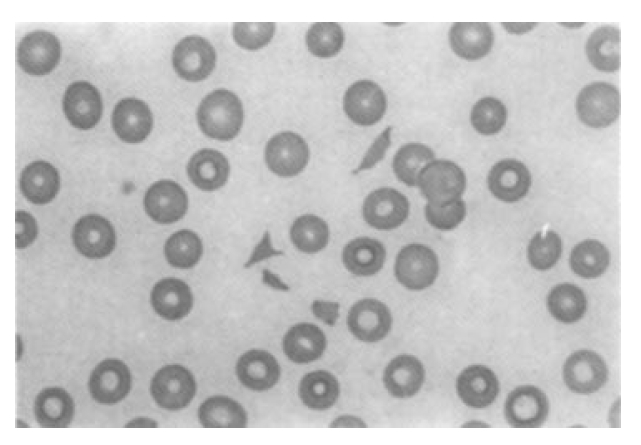

Fig. 1.

Positive C-ANCA in immunofluorescence testing(×100). Centrally accentuated finely granular cytoplasmic immunofluorescence is present in all neutrophils, with no stanining of neutrophil polymorphonuclear lobes.